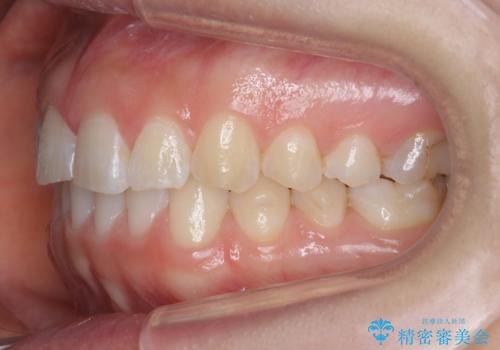

下の前歯のちょっとしたがたつきを治したい

- 下の前歯のがたつきを治したいとのことでした。

上の前歯のちょっとしたねじれも治療しています。

軽度だったため、部分矯正のコースで短期間で治療しました。

下の歯並びを並べるため、わずかに歯を削合しています。

そうしないと、前に出て上の前歯に強く当たってしまうためです。また、後戻りを防ぐ効果もあります。

年齢を重ねてくると、下の前歯が目立つようになるので治療しておくと若々しい印象を保つことができます。